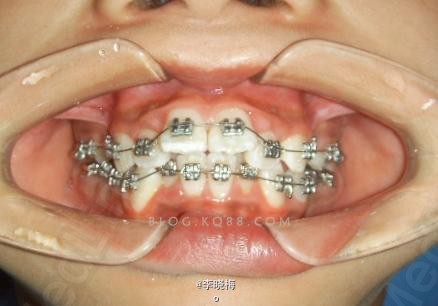

一例前牙Ⅲ度深覆盖的矫治

患者女,14岁,因“上牙前突影响面容”要求矫治,混合牙列,覆盖较大,9毫米,上颌两个门牙完全在牙弓弧度外,微笑时露龈,最棘手的是四个第一磨牙均大面积龋坏,我先将龋坏的磨牙根管治疗,桩核冠修复,拔除双侧上4及下颌Ⅴ,上颌加强支抗后用片段弓拉上颌3,后拔除双侧下颌4,经过一年多的矫治,解除了拥挤,内收了上下前牙,建立了正常的覆颌覆盖。(来源于网络)